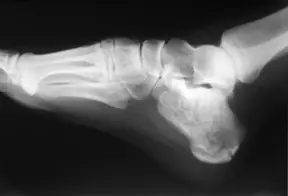

Fracture calcaneus, talus, autres os du tarse